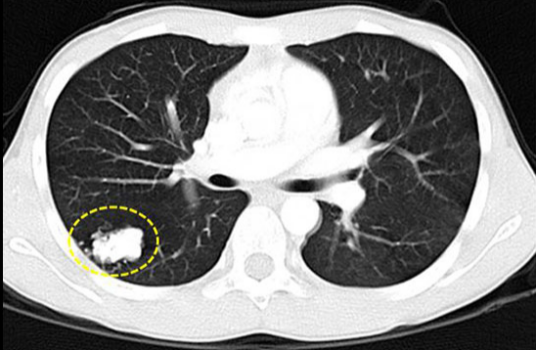

肺结节是指肺部影像上各种大小、边缘清楚或模糊、直径小于等于3cm的局灶性圆形致密影。